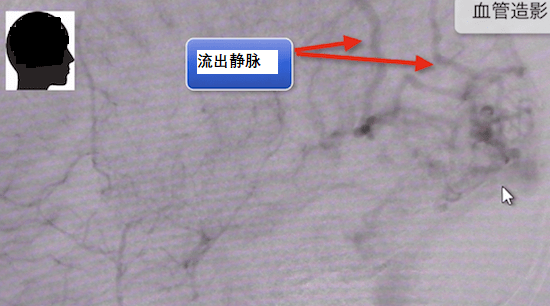

血管造影可清楚顯示病灶和流入動(dòng)脈。

您還可以檢查流出靜脈。

較終診斷為腦動(dòng)靜脈畸形。